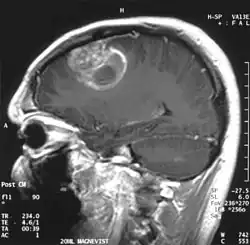

W obrazowaniu metodą rezonansu magnetycznego stwierdza się guz o niejednorodnym sygnale, ze współistniejącymi zmianami wstecznymi. Glejak wielopostaciowy ulega silnemu, nieregularnemu, brzeżnemu wzmocnieniu kontrastowemu.

W tomografii komputerowej guz objawia się w początkowym okresie jako ognisko hipodensyjne, nie ulega wzmocnieniu po podaniu kontrastu. Później współczynnik osłabienia jest zróżnicowany, ognisko ma nieregularne granice i otoczone jest szerokim pasmem obrzęku.